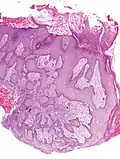

Microscopic image of the epidermis, which constitutes the outer layer of skin, shown here by the white bar

Microscopic image showing the layers of the epidermis. The stratum corneum appears more compact in this image than above because of different sample preparation.